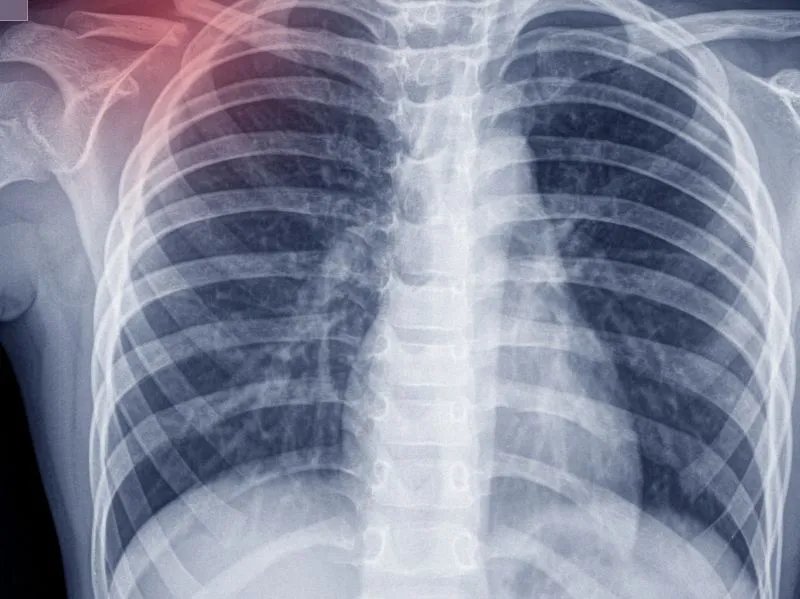

肺鳞癌多发于老年男性群体,且以中央型肺癌最为常见,肺鳞癌早期会引发阻塞性肺炎或者支气管炎。肺鳞癌也称肺鳞状上皮细胞癌,具有生长缓慢,转移晚的特点。肺鳞癌晚期的患者一般可以活三到六个月,但是如果得到较好的护理患者的存活时间会更长。